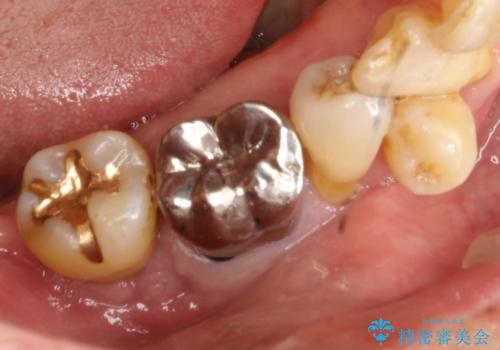

[歯周病治療] 歯周補綴 インプラント補綴

![[歯周病治療] 歯周補綴 インプラント補綴の症例 治療前](https://seimitsushinbi.jp/wp/wp-content/uploads/2020/03/067ed603e15bc4c623e950ffbd6c0829-500x350.jpg?v=1585493851)

![[歯周病治療] 歯周補綴 インプラント補綴の症例 治療後](https://seimitsushinbi.jp/wp/wp-content/uploads/2020/03/93a1bf8bd8e0f11621dbb40f6f1d795c-500x350.jpg?v=1585494318)